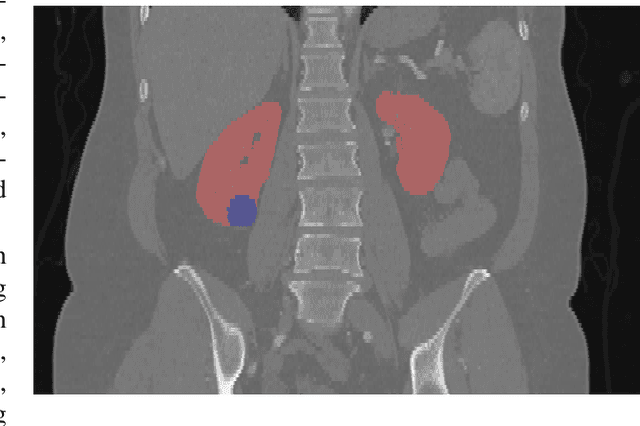

Abstract:Kidney cancer is a global health concern, and accurate assessment of patient frailty is crucial for optimizing surgical outcomes. This paper introduces AI Age Discrepancy, a novel metric derived from machine learning analysis of preoperative abdominal CT scans, as a potential indicator of frailty and postoperative risk in kidney cancer patients. This retrospective study of 599 patients from the 2023 Kidney Tumor Segmentation (KiTS) challenge dataset found that a higher AI Age Discrepancy is significantly associated with longer hospital stays and lower overall survival rates, independent of established factors. This suggests that AI Age Discrepancy may provide valuable insights into patient frailty and could thus inform clinical decision-making in kidney cancer treatment.

Abstract:This paper presents the challenge report for the 2021 Kidney and Kidney Tumor Segmentation Challenge (KiTS21) held in conjunction with the 2021 international conference on Medical Image Computing and Computer Assisted Interventions (MICCAI). KiTS21 is a sequel to its first edition in 2019, and it features a variety of innovations in how the challenge was designed, in addition to a larger dataset. A novel annotation method was used to collect three separate annotations for each region of interest, and these annotations were performed in a fully transparent setting using a web-based annotation tool. Further, the KiTS21 test set was collected from an outside institution, challenging participants to develop methods that generalize well to new populations. Nonetheless, the top-performing teams achieved a significant improvement over the state of the art set in 2019, and this performance is shown to inch ever closer to human-level performance. An in-depth meta-analysis is presented describing which methods were used and how they faired on the leaderboard, as well as the characteristics of which cases generally saw good performance, and which did not. Overall KiTS21 facilitated a significant advancement in the state of the art in kidney tumor segmentation, and provides useful insights that are applicable to the field of semantic segmentation as a whole.

Abstract:There is a large body of literature linking anatomic and geometric characteristics of kidney tumors to perioperative and oncologic outcomes. Semantic segmentation of these tumors and their host kidneys is a promising tool for quantitatively characterizing these lesions, but its adoption is limited due to the manual effort required to produce high-quality 3D segmentations of these structures. Recently, methods based on deep learning have shown excellent results in automatic 3D segmentation, but they require large datasets for training, and there remains little consensus on which methods perform best. The 2019 Kidney and Kidney Tumor Segmentation challenge (KiTS19) was a competition held in conjunction with the 2019 International Conference on Medical Image Computing and Computer Assisted Intervention (MICCAI) which sought to address these issues and stimulate progress on this automatic segmentation problem. A training set of 210 cross sectional CT images with kidney tumors was publicly released with corresponding semantic segmentation masks. 106 teams from five continents used this data to develop automated systems to predict the true segmentation masks on a test set of 90 CT images for which the corresponding ground truth segmentations were kept private. These predictions were scored and ranked according to their average So rensen-Dice coefficient between the kidney and tumor across all 90 cases. The winning team achieved a Dice of 0.974 for kidney and 0.851 for tumor, approaching the inter-annotator performance on kidney (0.983) but falling short on tumor (0.923). This challenge has now entered an "open leaderboard" phase where it serves as a challenging benchmark in 3D semantic segmentation.

Abstract:The morphometry of a kidney tumor revealed by contrast-enhanced Computed Tomography (CT) imaging is an important factor in clinical decision making surrounding the lesion's diagnosis and treatment. Quantitative study of the relationship between kidney tumor morphology and clinical outcomes is difficult due to data scarcity and the laborious nature of manually quantifying imaging predictors. Automatic semantic segmentation of kidneys and kidney tumors is a promising tool towards automatically quantifying a wide array of morphometric features, but no sizeable annotated dataset is currently available to train models for this task. We present the KiTS19 challenge dataset: A collection of multi-phase CT imaging, segmentation masks, and comprehensive clinical outcomes for 300 patients who underwent nephrectomy for kidney tumors at our center between 2010 and 2018. 210 (70%) of these patients were selected at random as the training set for the 2019 MICCAI KiTS Kidney Tumor Segmentation Challenge and have been released publicly. With the presence of clinical context and surgical outcomes, this data can serve not only for benchmarking semantic segmentation models, but also for developing and studying biomarkers which make use of the imaging and semantic segmentation masks.